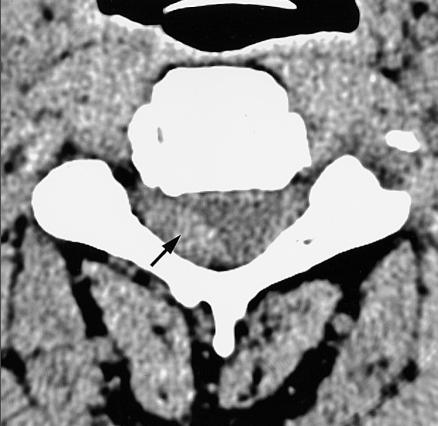

Pure epidural cavernous hemangioma of the cervical spine that presented with an acute sensory deficit caused by hemorrhage.

Pure epidural cavernous hemangioma of the spine without vertebral involvement is rare. Due to the slow growth of this lesion, the most common symptoms are chronic pain, myelopathy, and radiculopathy. In our case, the patient complained of an acute onset sensory deficit of the C4 dermatome. An MRI revealed an epidural mass with an acute hematoma. Here, we report a case of a pure epidural cavernous hemangioma that presented with acute neurologic symptoms caused by intralesional hemorrhage and an acute epidural hematoma, which were demonstrated on the patient's MRI.